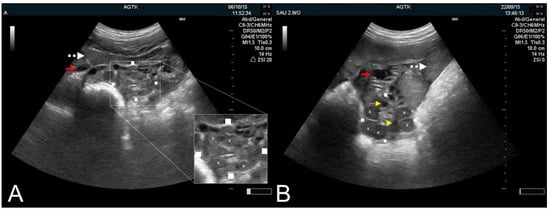

3.1.2. The Puerperal Uterus